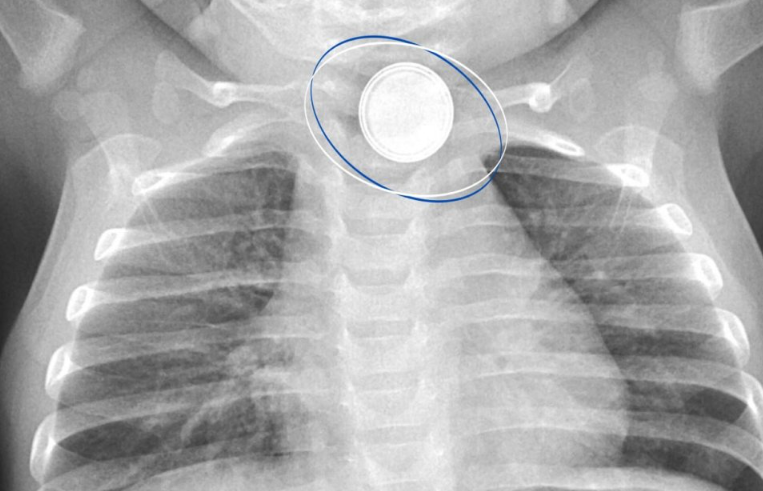

В Сургуте врачи успешно достали из пищевода 11-месячного малыша круглую батарейку, которую тот проглотил. Родители вызвали скорую помощь сразу, когда заметили опасную ситуацию, пишет ugra-news.ru. Сначала ребенка доставили в больницу Нефтеюганска, где рентген показал инородный предмет в пищеводы. Малыша экстренно доставили в Центр охраны материнства и детства Сургута. Обследование показало, что у маленького пациента серьезный ожог пищевода от батарейки диаметром 1,5 см. Пишут журналисты. Врачи провели срочную операцию. Хирург Эльнур Джафаров совместно с коллегами удалил опасный предмет. Малышу понадобился месяц на восстановление, сейчас он чувствует себя хорошо и уже находится дома. Даже безобидные на первый взгляд предметы могут быть смертельно опасны. Нельзя откладывать обращение за медпомощью – каждая минута может спасти жизнь. Считает глава Центра Лариса Белоцерковцева. Ранее врачи Тюменской областной инфекционной клинической больницы вылечили младенца с тяжёлым диагнозом — пневмок

Сначала ребенка доставили в больницу Нефтеюганска, где рентген показал инородный предмет в пищеводы. Малыша экстренно доставили в Центр охраны материнства и детства Сургута. Обследование показало, что у маленького пациента серьезный ожог пищевода от батарейки диаметром 1,5 см. Пишут журналисты.